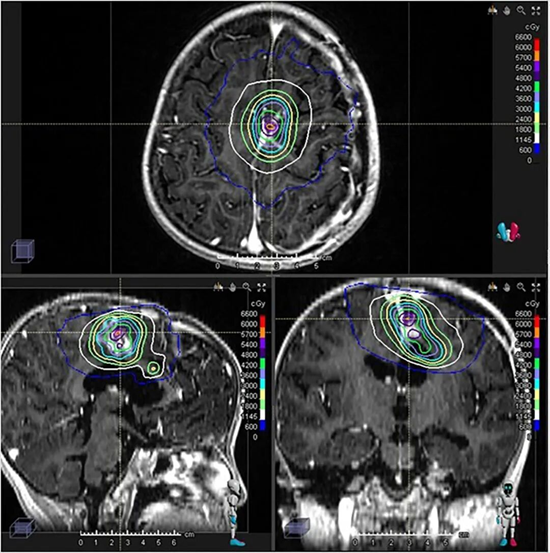

伽马刀立体定向放射外科治疗计划和剂量分布。剂量为30Gy/5次。

在质子治疗后,团队曾采用靶向药物治疗以稳定病情。由于仍有少量肿瘤残留,在进行二次手术后,团队果断启用伽马刀(GKRS)进行“最后一击”。正是得益于前期质子治疗对周围正常组织的良好保护,才使得后续高剂量的、高度聚焦的伽马刀治疗得以安全、有效地实施,最终对残余病灶进行了彻底处理。